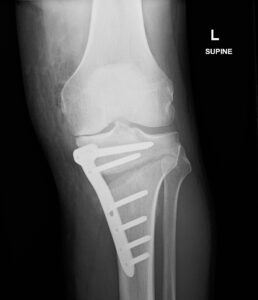

Knee Procedures Total Knee Replacement A knee replacement is a surgical procedure in which damaged or worn-out parts of the knee joint are removed and replaced with artificial components. It is typically done to reduce pain and improve function in people with severe knee joint damage, often caused by arthritis or injury. Partial Knee Replacement A knee replacement is a surgical procedure in which damaged or worn-out parts of the knee joint are removed and replaced with artificial components. It is typically done to reduce pain and improve function in people with severe knee joint damage, often caused by arthritis or injury. Revision Knee Replacement Revision knee replacement is a surgical procedure to replace or repair a previous knee prosthesis that has become loose, worn out, or infected. It involves removing the old implant and installing a new one to restore knee function and relieve pain. High Tibial Osteotomy High tibial osteotomy is a surgery that involves cutting and reshaping the upper part of the shinbone (tibia) to realign the knee joint. It is often performed to relieve arthritis pain in young, active patients by shifting weight away from damaged cartilage. ACL Reconstruction ACL reconstruction is a surgical procedure to replace a torn anterior cruciate ligament (ACL) in the knee with a graft, usually taken from the patient's own tissue or a donor. It aims to restore stability and allow return to normal activity levels following ligament injury. Meniscal Surgery Meniscal surgery involves repairing or removing damaged meniscal cartilage in the knee, which cushions and stabilizes the joint. The procedure can help relieve pain, restore knee function, and prevent further joint degeneration. Patellofemoral Stabilisation Patellofemoral stabilisation is a procedure to realign or secure the kneecap (patella) when it tends to dislocate or drift out of place. It aims to improve knee stability and prevent recurrent dislocations or pain.